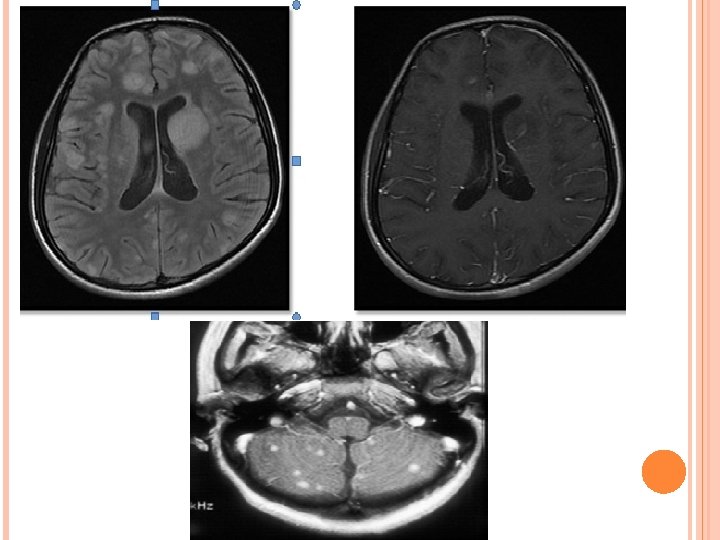

HIV ENCEPHALITIS NECT- Normal or atrophy +/- WM hypodensity. MR • • • v Volume loss with prominent sulci and ventricle. T 2/FLAIR hazy symmetric WM hyperintensity, spare the subcortical U fibers. No mass effect. Usually no enhancement and no restricted diffusion. T 1 images reveal no hypointensity. Reduced grey matter volume in superior and medial frontal gyri – possible early imaging marker. D/D- PML, CMV enchephalitis, ventriculitis; toxoplasmosis; Herpes and HHV-6 encephalitis.

PROGRESSIVE MULTIFOCAL LEUKOENCEPHALOPATHY • ETIOLOGY- JC virus. Ubiquitous virus. Immunodificiency. Most common predisposing condition = HIV (80%). • Three phases of devlopment. Virus exclusively affect the oligodendrocytes. Multifocal demyelination. Predominantly affect parietal & occipital lobes. posterior fossa white matter and basal ganglia involvement is also present. CNS manifestation are c. PML , i. PML, JC encephalitis/meningitis.

IMAGING: Multifocal WM lesions but may be unifocal. Bilaterally assymetric. Involve subcortical U fibers. Spare cortex. No mass effect/enhancement (except i. PML) On DWI, varies according to disease stage. MRS- Decrease NAA, increased choline and lipid lactate peak. p. MRI – shows reduced r. CBV. D/D- HIVE, PML-IRIS, CMV.